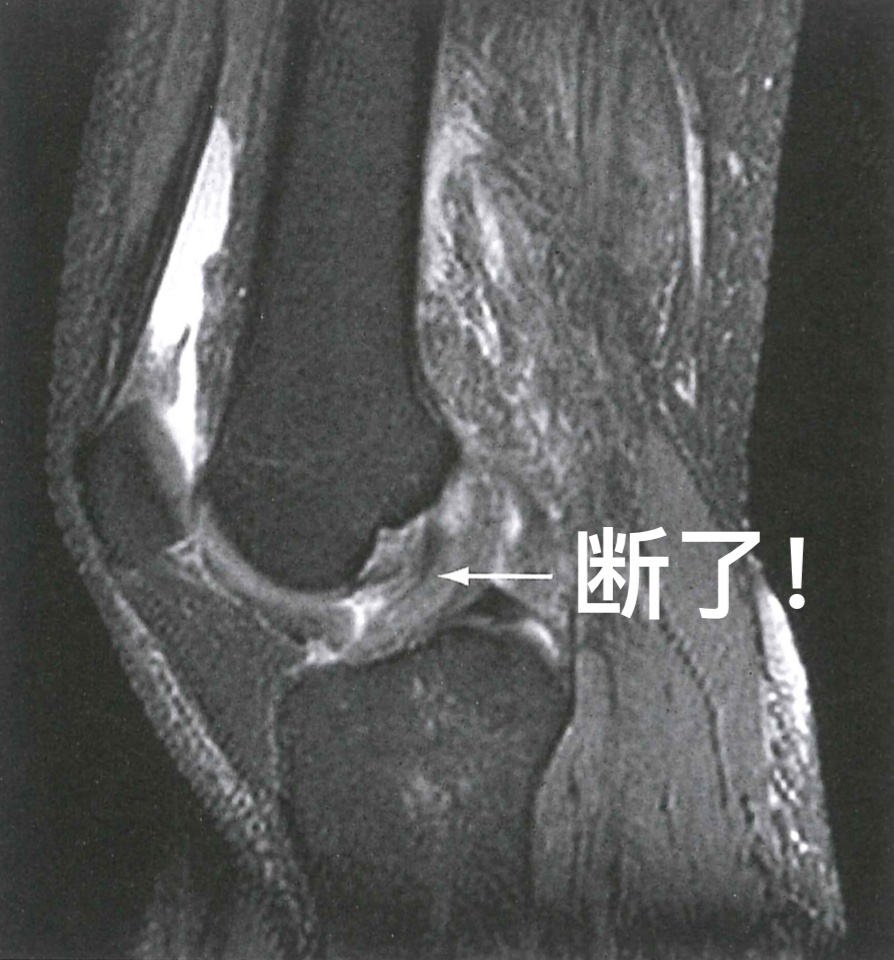

图 3 前交叉韧带损伤

比如在打羽毛球时,一个扣杀好不精彩,但若是落地不慎,膝关节马上就让你无精打采,只能暂停一下,对比赛不理不睬。X线做完只告诉你没有骨折,但膝关节痛得让你实在没辙,只能再次来到影像科。膝关节MRI一做发现,前交叉韧带断了!